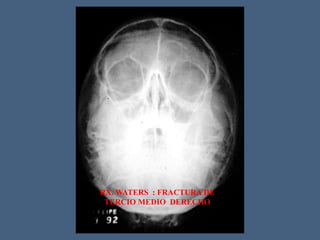

RX. WATERS : FRACTURA DE

TERCIO MEDIO DERECHO

RX. WATERS :FRACTURA DE TERCIO MEDIO DERECHO